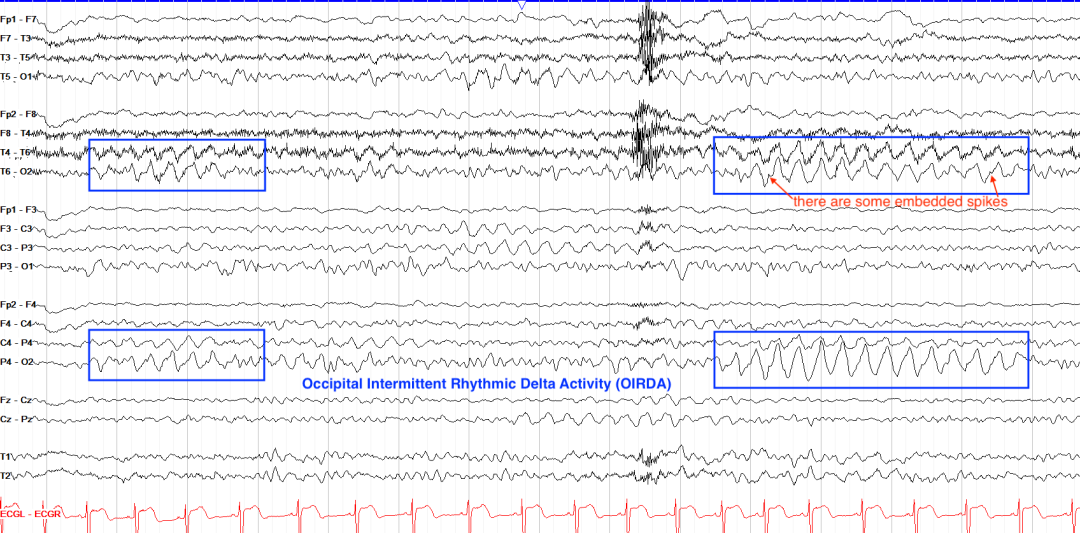

3.枕叶癫痫(Occipital Lobe Epilepsy)

临床关联:多见于儿童,表现为枕区优势的节律性δ波,与儿童良性癫痫或结构性病变相关。

波形特征:

后头部优势的节律性尖波或快活动,闭眼易诱发。

发作期常伴视觉先兆(闪光、盲点)。

枕区优势的节律性δ波